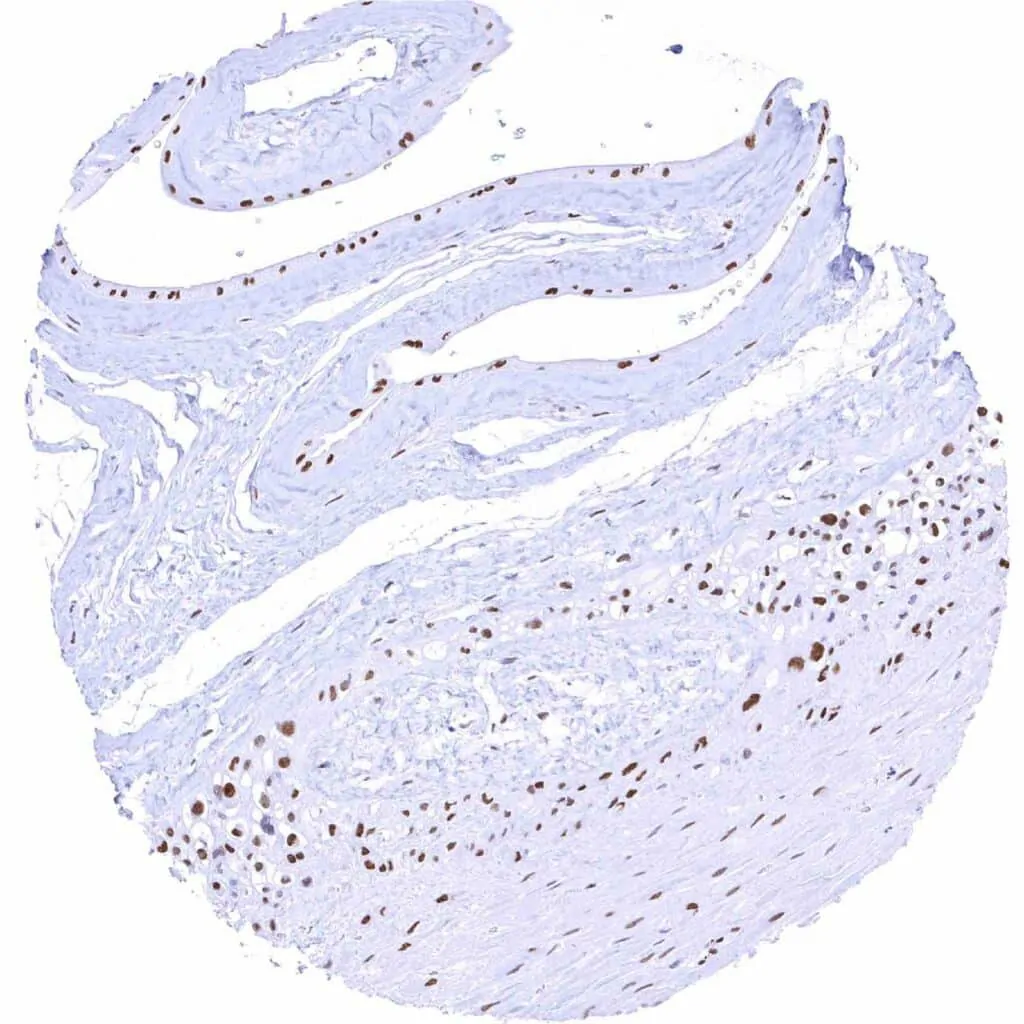

Aorta, media – Moderate TLE1 positivity of a subset of spindle cells in the media